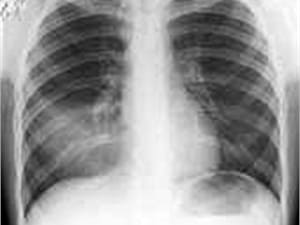

Пневмококковая пневмония

Пневмония характеризуется высокой температурой - подъемом до высоких (фебрильных) цифр – 38-39°, ознобом, выраженной слабостью, мышечными болями, одышкой, учащенным сердцебиением; вскоре появляется влажный кашель с мокротой слизисто-гнойного характера (по цвету желтовато-зеленоватая), порой при кашле беспокоят боли в грудной клетке.

Пневмония при пневмококковой инфекции могжет быть крупозной (внезапное начало, высокая температура, выраженные ознобы, румянец на щеках, резкие боли в грудной клетке и мокрота с коричневым оттенком – «ржавая», при выслушивании влажные хрипы, крепитация, «шум трения плевры», притупление перкуторного звука) или очаговой (возникает на фоне проявлений острой респираторной инфекции – появляется слабость, влажный кашель, потливость, одышка, мокрота слизисто-гнойная, боли в небольшом участке грудной клетки, бледность кожных покровов, выслушиваются мелко и среднепузырчатые хрипы). Крупозная пневмония протекает тяжелее, возможно развитие острой дыхательной недостаточности, формирование абсцессов, плеврита.

Очаговая пневмония легче по тяжести, однако инфильтрация рассасывается в более длительный срок – до 4х недель.